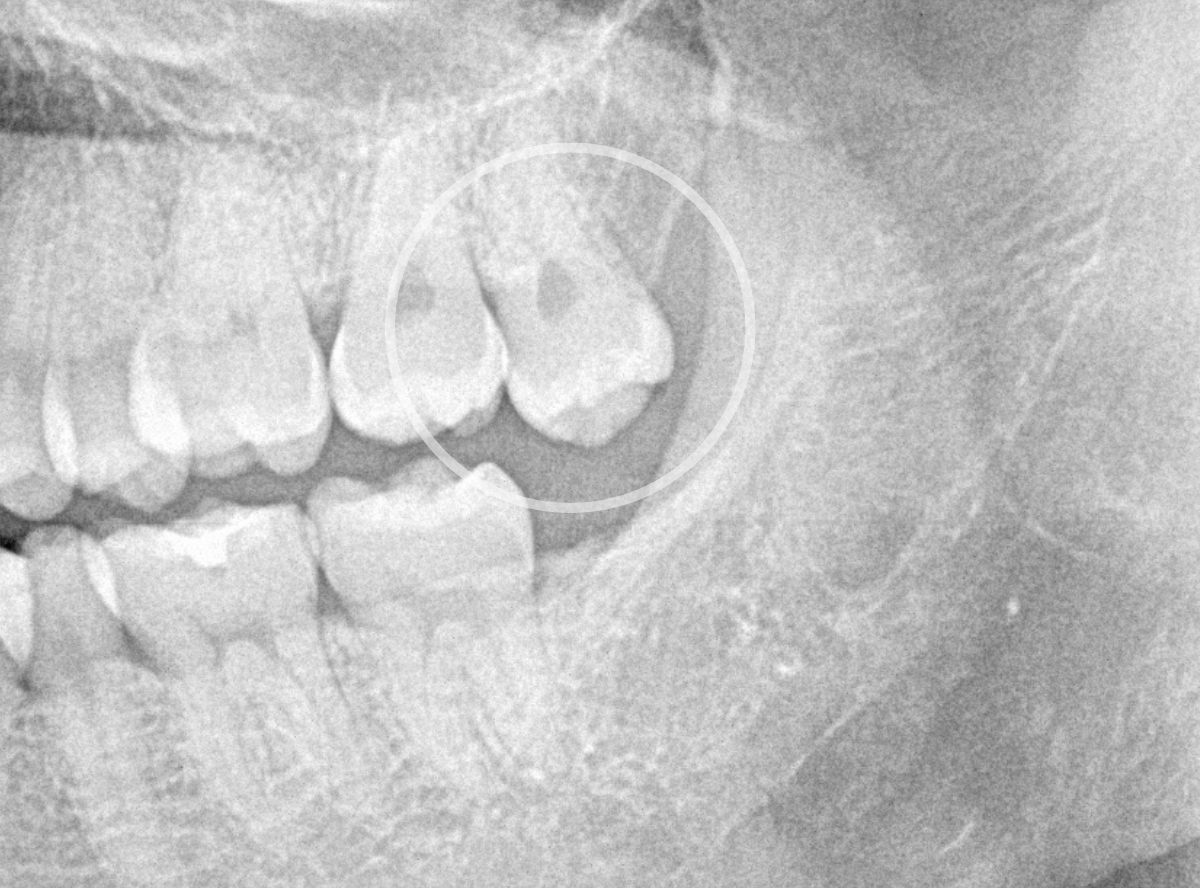

ここでは、比較的簡単なおやしらずの抜歯の例を中心にご紹介します。

このようなおやしらず、あなたはありませんか?